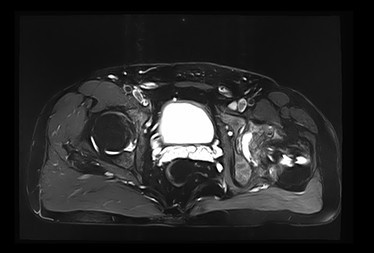

查体:左髋外侧可见一约25cm手术瘢痕,其上可见一点状结痂,左腿较右腿短缩,左腿肌肉较右腿萎缩,步态异常。左髋部无压痛,左腿外侧感觉异常,以左膝外侧为重,左髋外侧叩击痛,左足背动脉搏动未扪及异常。左下肢较右下肢短缩约2cm,左髋关节活动受限,其余各关节未见明显异常。 辅查:MRI示左股骨头坏死

诊断:左股骨头股骨颈粉碎性骨折切开复位内固定术后坏死 治疗:择期行关节置换术

股骨头坏死是一个病理演变过程,初始发生在股骨头的负重区,应力作用下坏死骨骨小梁结构发生损伤即显微骨折以及随后针对损伤骨组织的修复过程。造成骨坏死的原因不消除,修复不完善,损伤-修复的过程继续,导致股骨头结构改变、股骨头塌陷、变形,关节炎症,功能障碍。